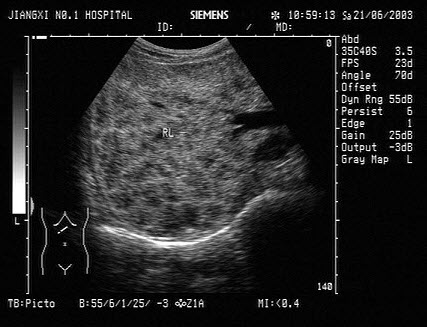

65、单项选择题

结合超声图像,该病例肾结石为哪一部位()

A.下极肾盏

B.中极肾盏

C.上极肾盏

D.肾门

E.肾乳头处